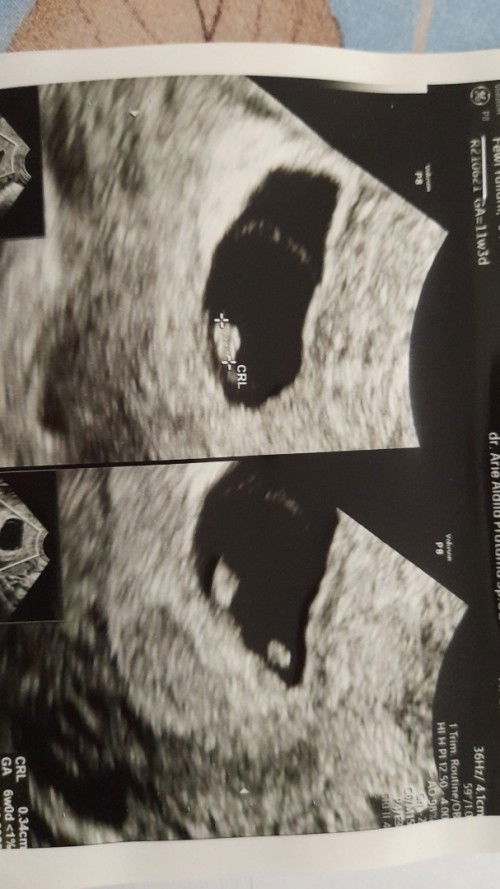

Aku usg usia kehamilan 9 week , janin sudah ada tpi sngat kecil uk 0,3 cm, denyut jantung belum ada, dan skrang lagi flek kta dokter janinnya kematian mudigah dan disarankan oleh dokter dikuret, Ini khamilan pertama aku, bagusnya gimana bunda2 Apakah ngikutin saran dari dokternya atau menunggu dlu dg mnum obat pnguat kanduangan Aku bingung#seriusnanya #bantusharing